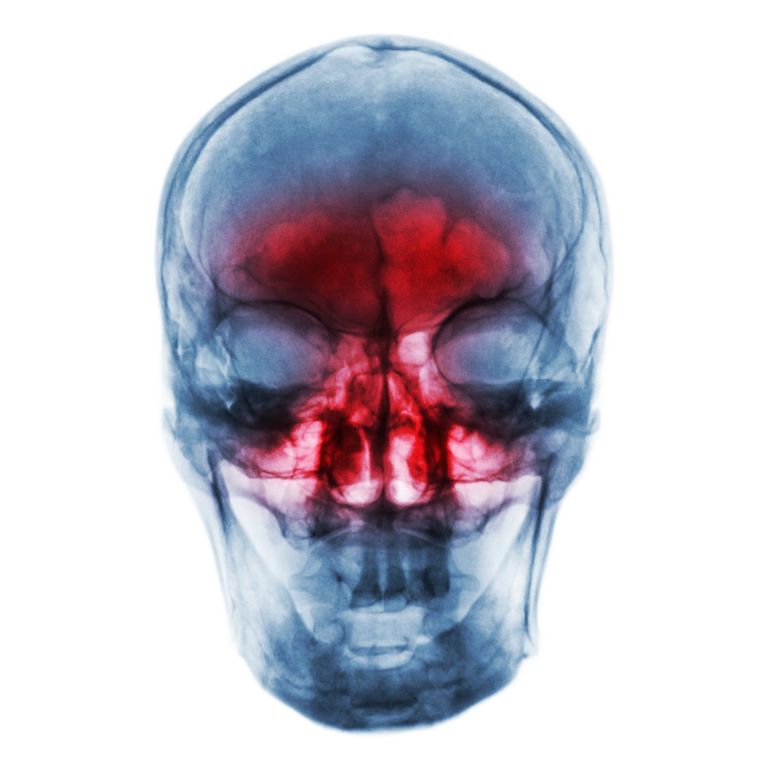

Širjenje vnetja nosne sluznice se lahko razvije v akutno vnetje sinusov. Dobro je prepoznati znake in preprečiti razvoj vnetja v resne zaplete.

Akutno vnetje sinusov ali akutni sinusitis lahko nastane brez predhodnega vnetja nosne sluznice, najpogosteje pa se razvije zaradi stopnjevanja prehlada. Pojavlja se v dveh oblikah in sicer v virusni in bakterijski obliki. Preverimo, kateri simptomi nakazujejo na vnetje, zakaj do slednjega sploh pride in kaj se zgodi, če razvoja bolezni ne zaustavimo.

Gnojni sinusitis zdravnik zdravi s čiščenjem in zračenjem sinusov. Potrebno je zmanjšanje otekline in odpravljanje bakterij. Nezdravljen sinusitis lahko vodi v resne zaplete, poleg trajnega kroničnega vnetja lahko namreč vnetje povzroči posledice na kosteh, v očesni votlini, v hujših primerih pa tudi na možganih.

skelet glave, sinusi.jpg

skelet glave, sinusi